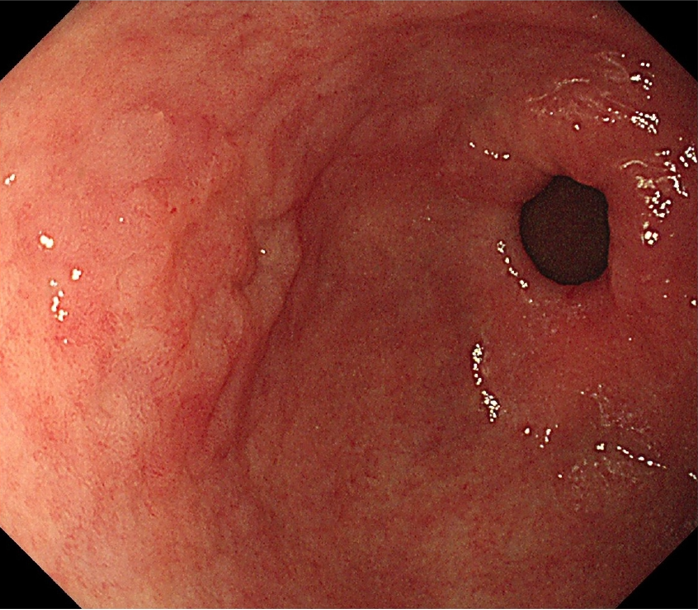

(1) 위내시경 검사

위축성 위염의 기본적인 진단은 위내시경 검사를 통해 이루어집니다. 내시경 검사 시 다음과 같은 특징적인 소견이 관찰됩니다:

- 위점막이 얇아진 상태

- 점막의 창백함

- 점막의 반짝거림

- 점막 아래 혈관이 투명하게 보임

- 위 주름의 감소